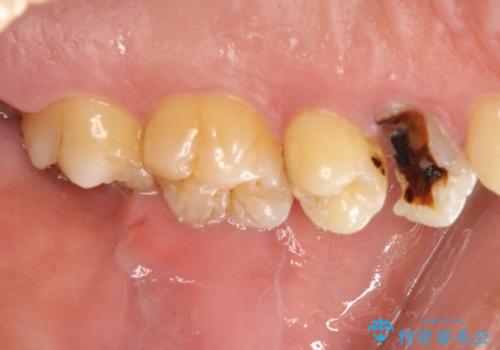

大きな虫歯で崩壊した歯の修復

虫歯で奥歯が真っ黒になり崩壊していましたが、悪い部分を完全に取り除き、丁寧に修復することでまた長く機能させることができます。